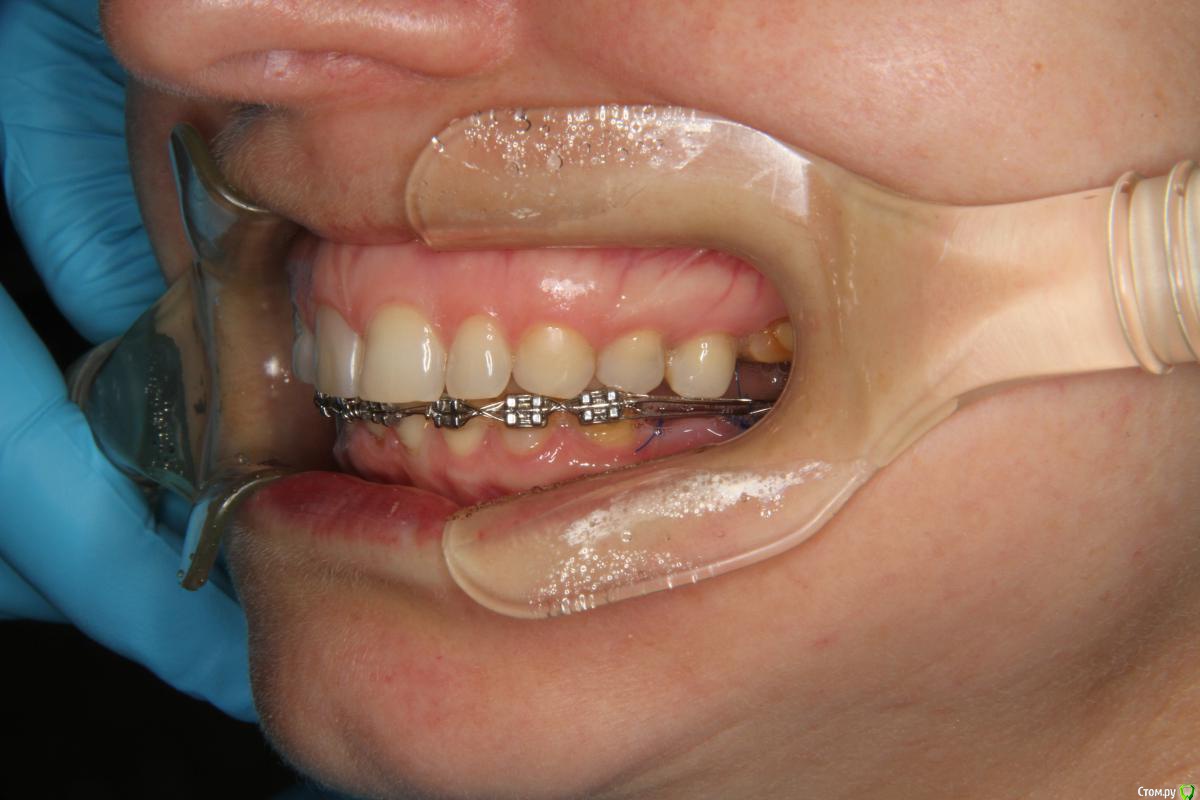

Yana guapa Опубликовано 3 сентября, 2015 Поделиться Опубликовано 3 сентября, 2015 Да, по перекрытию я смотрела, пространство (небольшое) есть. Я думаю, я еще сама связками (8-ками) заузила. Про ВЧ речь идет?Были брекеты вверху? Сейчас все зубы залигировала по одному и, действительно, попробую прямоугольную дугу- торк пойдет (брекеты на резцах 0*) может быть за счет этого расправятся.... не думаю, что это поможет. при отсутвие должного оверджета не получится протрузии, а значит и разворачиваться некуда будет. и прямоугольная дуга не поможет при таком дефиците места. процесс пойдет только тогда, когда появится место. это либо 1. создание оверджета (за счет ВЧ), или 2. сепарация НЧ 3. как вариант дистализация премоляров (если окклюзионные контакты позволяют (как сейчас по прикусу в боковых отделах? есть фото?) ) Ссылка на комментарий

Monkey Опубликовано 6 сентября, 2015 Автор Поделиться Опубликовано 6 сентября, 2015 Про ВЧ речь идет?Были брекеты вверху? не думаю, что это поможет. при отсутвие должного оверджета не получится протрузии, а значит и разворачиваться некуда будет. и прямоугольная дуга не поможет при таком дефиците места. процесс пойдет только тогда, когда появится место. это либо 1. создание оверджета (за счет ВЧ), или 2. сепарация НЧ 3. как вариант дистализация премоляров (если окклюзионные контакты позволяют (как сейчас по прикусу в боковых отделах? есть фото?) ) Нет, брекетов на вч не было. Фотографии боковых отделов есть только июньские. Дистализировать там больше нельзя.Выходит вариант один - сепарировать весь фронт? Ссылка на комментарий

Yana guapa Опубликовано 7 сентября, 2015 Поделиться Опубликовано 7 сентября, 2015 Дистализировать там больше нельзя.Выходит вариант один - сепарировать весь фронт? или ставить брекеты наверх)) справа 2 класс, ротирована НЧ вправо походу. (средние линии не совпадают, а при открытии рта выравниваются). у вас все равно компромиссное лечение (не до идеала, судя по бугорковому смыканию, наличию 8-к, заваленным 7-кам,....), то тогда и посепарировать можно. по-другому не впихнуть резцы. 1 Ссылка на комментарий

Monkey Опубликовано 7 сентября, 2015 Автор Поделиться Опубликовано 7 сентября, 2015 или ставить брекеты наверх)) справа 2 класс, ротирована НЧ вправо походу. (средние линии не совпадают, а при открытии рта выравниваются). у вас все равно компромиссное лечение (не до идеала, судя по бугорковому смыканию, наличию 8-к, заваленным 7-кам,....), то тогда и посепарировать можно. по-другому не впихнуть резцы. думаю там преждевременный контакт на 8-ке левой, вот она и скатывается. Яна, спасибо большое за советы! Ссылка на комментарий

Yana guapa Опубликовано 7 сентября, 2015 Поделиться Опубликовано 7 сентября, 2015 думаю там преждевременный контакт на 8-ке левой, вот она и скатывается. так удаляйте их! )) и на имплантах ( и коронках, думаю вы их тоже там планирует) поднимите немного прикус. Напрашивается. + Не будет такого плотного контакта на резцах Ссылка на комментарий

Maverick Опубликовано 9 сентября, 2015 Поделиться Опубликовано 9 сентября, 2015 Можно подвергнуть сепарации нижний зубной ряд от премоляра до премоляра. Места будет валом тогда резцам. Плюс с резцов меньше сошлифуете. Ссылка на комментарий